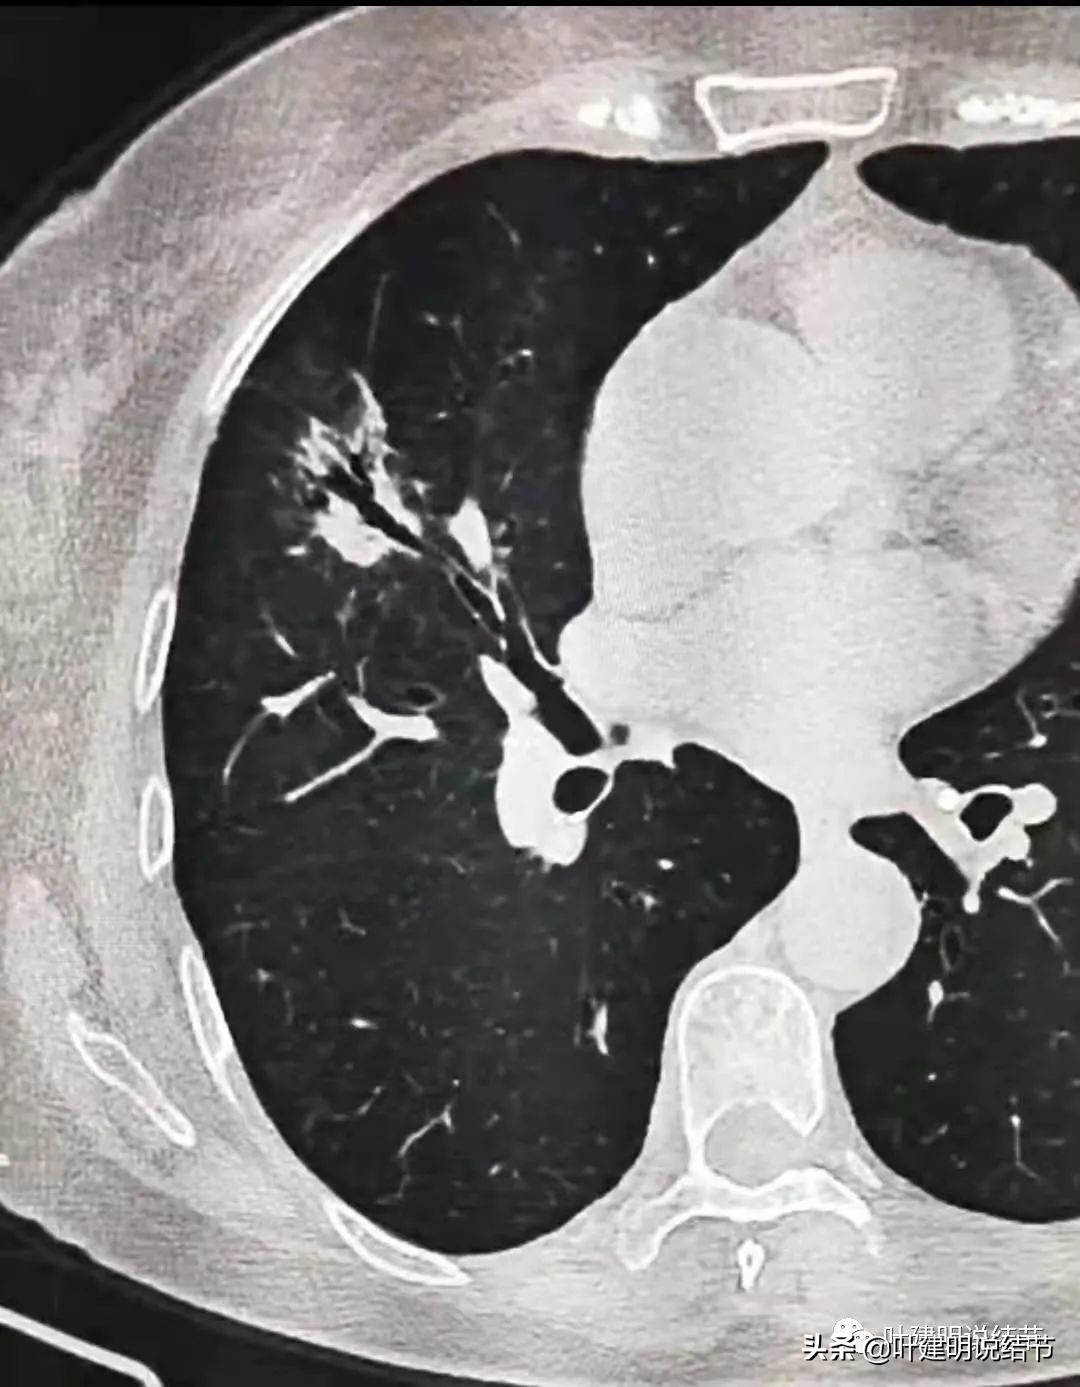

这是2020年11月时的,见病灶显混合磨玻璃,分叶明显(砖色箭头)、整体轮廓较清(红色箭头)、实性成分占比较多,相对有点散,不是特别致密(粉色箭头)、磨玻璃成分分布全部病灶,轮廓还算清,边缘略糊(绿色箭头)。这样的影像表现如果更聚拢一点,就是典型的浸润性腺癌的混合磨玻璃表现。